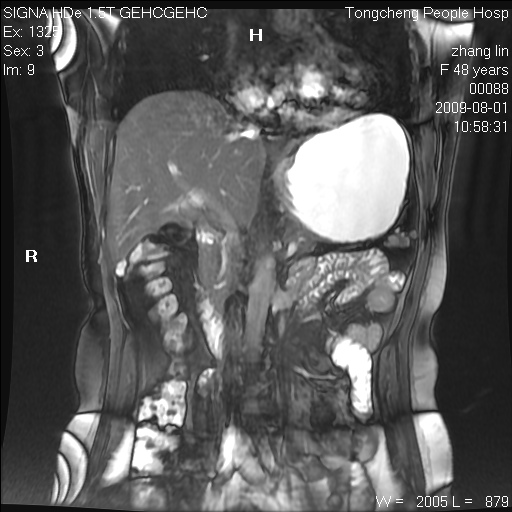

女,48岁。健康体检,彩超发现右肾占位性病变。平素健康。

临床诊断:右肾占位性病变,性质待定(囊肿?肿瘤?)。

上中腹部mr平扫+增强扫描,图像如下:

右肾上极见一类圆形病灶,t1wi呈等信号t2wi呈等高混杂信号,三期增强无强化,边界清---考虑囊肿出血。